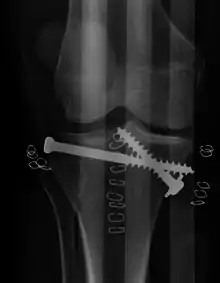

![]() | |

| A severe tibial plateau fracture with an associated fibular head fracture | |

Pain may be managed with NSAIDs, opioids, and splinting.[2][3] In those who are otherwise healthy, treatment is generally by surgery.[2] Occasionally, if the bones are well aligned and the ligaments of the knee are intact, people may be treated without surgery.[3] The surgery usually involves reducing the fractured fragments of the tibia plateau to their anatomical position and fixing them in place with screws only or fixed angle anatomical plates ensuring absolute stability. Implant selection is based on the type of injury. Generally, simple or incomplete fractures (Schatzker type 1) of the plateau are compressed with 6.5mm partially threaded cancellous screws. Complex type fractures will require a plate for enhanced stability. As the tibia condyles articulate with the femur (thigh bone) to form knee joint, any incongruity in the articular surface is unacceptable as it leads to early arthritis. Prolonged immobilization of the knee joint is also not recommended which result in stiffness of the joint and difficult recovery.